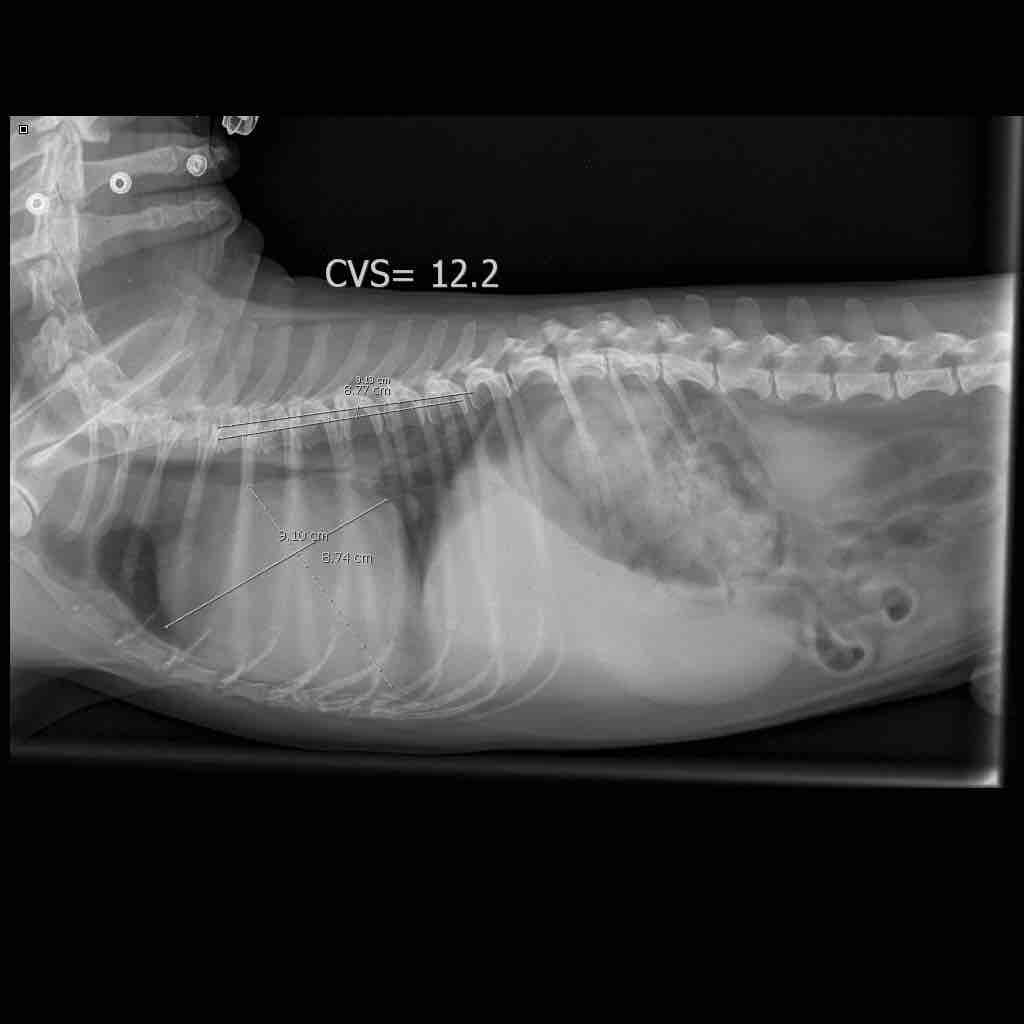

My dog is suffering from enlarged spleen. His lower stomach is a bit enlarged and he sneezes every once in a while. Also his breathing is a bit heavy and in some cases I can hear him trying to breath deeply two or three times in a row. Is there some medication to help him with the spleen issue? I cannot relay on vets in my current location as animal care is not that common to them

Enlarged spleens can occur for many reasons including immune mediated disease, infections and tumours and the treatment for each is quite different. Blood tests to rule out infections and removal and biopsy of the spleen are often used to investigate. There is no single treatment which would be expected to be curative but a well balanced diet is recommended